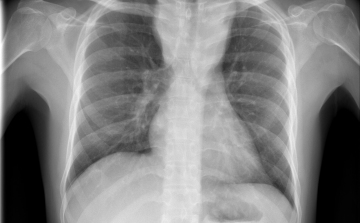

Már a 26. tüdőátültetést végezték el Magyarországon

A 26. tüdőátültetést végezték el Magyarországon a közelmúltban - közölte az Országos Onkológiai Intézet és a Semmelweis Egyetem hétfőn az MTI-vel.

Elvégezték az első magyar tüdő- és vesetranszplantációt egy műtét keretében

Elvégezték az első magyarországi tüdő- és vesetranszplantációt egy műtét keretében június 30-án - tudatta az Országos Onkológiai Intézet hétfőn az MTI-vel.

Elhagyhatta a kórházat az első magyarországi tüdőátültetésen átesett férfi

Jó általános állapotban elhagyhatta az Országos Onkológiai Intézetet (OOI) az a férfi, akin először hajtottak végre tüdőtranszplantációt Magyarországon.

Először hajtottak végre tüdőtranszplantációt Magyarországon

Először hajtottak végre tüdőtranszplantációt Magyarországon, a műtét sikeres volt - jelentették be az operációt végző szakemberek és az Országos Onkológiai Intézet vezetője szombaton Budapesten.

Idén elvégezhetik az első hazai tüdőátültetést

Idén elvégezhetik az első hazai tüdőátültetést - mondta el Mihály Sándor, az Országos Vérellátó Szolgálat Szervkoordinációs Irodájának igazgatója az M1 aktuális csatorna szerdai műsorában.

Húszan várnak tüdőátültetésre Magyarországon

Húszan várnak tüdő-transzplantációra az országban, tavaly 12 magyar betegen hajtottak végre ilyen szervátültetést külföldön